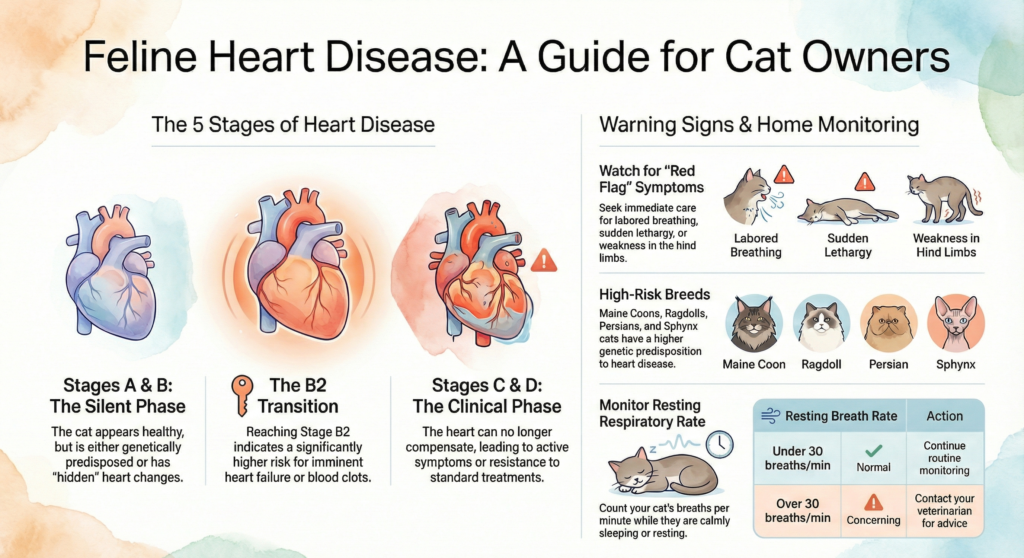

In most cats, the exact cause is unknown (idiopathic). However, we know that certain pedigree breeds, such as Maine Coons, Ragdolls, and Persians, are at higher risk, and specific genetic mutations have been identified in Maine Coons and Ragdolls. Additionally, other conditions like hyperthyroidism or high blood pressure can cause the heart muscle to thicken, mimicking the appearance of HCM.

- Labored or heavy breathing: This is the most common sign and often indicates fluid buildup in the lungs or chest (congestive heart failure).

- Lethargy or hiding: Cats may become less active or hide more than usual.

- Sudden weakness or paralysis: Specifically in the hind limbs, which may be caused by a blood clot (arterial thromboembolism).

What are the stages for HCM? We use a staging system to determine the severity of the disease and guide treatment:

- Stage A: Cats at high risk for developing the disease (e.g., specific breeds or those with a known genetic mutation) but who currently have healthy hearts.

- Stage B1: Cats with HCM who are at low risk for immediate complications.

- Stage B2: Cats with HCM who are at a higher risk for heart failure or blood clots, typically identified by an enlarged left atrium.

- Stage C: Cats that currently have, or previously had, clinical signs of heart failure or blood clots.

- Stage D: Cats with advanced heart failure that is no longer responding well to standard therapy.

- Resting Respiratory Rate (RRR): This is the most important tool for owners. Count how many breaths your cat takes per minute while they are calmly sleeping. A consistent rate under 30 breaths per minute is the goal. If the rate is consistently rising or exceeds 30, seek medical attention immediately.